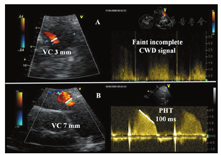

目前尚缺乏评价人工肺动脉瓣反流(PR)的影像学资料。对人工瓣PR的检出几乎全部要依赖彩色血流显像,当RVOT内测及流向RV的舒张期血流时即诊断为PR。

与轻度PR相比,显著人工瓣PR反流表现为血流持续时间更长(全舒张期)、跨肺动脉瓣的反流束更宽[173]。但是在重度PR患者,当舒张期肺动脉压力与RV压力的平衡点出现在舒张早期时,彩色反流区域显示可非常短暂和不准确(依赖于驱动压)[174]。人工瓣PR程度的评价通常根据反流束在起源处的宽度来估测[175,176,177]。彩色反流束最大直径(宽度)在胸骨旁短轴切面或肋下切面紧邻肺动脉瓣下(RVOT与肺动脉瓣环交界处)于舒张期进行测量。尽管存在明显的观察者间变异,当反流束宽度大于同帧测量的RVOT直径的50%~65%时提示重度PR。肺动脉内测及逆向彩色多普勒血流时是中至重度PR的特异性表现[14,20]。

尽管采用彩色多普勒的缩流束宽度可能比反流束宽度对PR程度的评价更为准确,但缺乏相关证据。在某些患者中可采用血流汇聚带来评价,但其定量PR程度的临床准确性尚未得到证实。

PHT缩短(<100 ms)(由于血流快速下降终止于舒张中晚期,CW多普勒信号呈正弦波形)和浓密的CW频谱对诊断重度PR虽无特异性,但可出现在重度PR患者中[178,179]。PHT不仅受PR程度的影响,还与舒张期肺动脉内压力和RV舒张期特性有关,当RV呈限制性充盈时,PHT缩短更加显著。